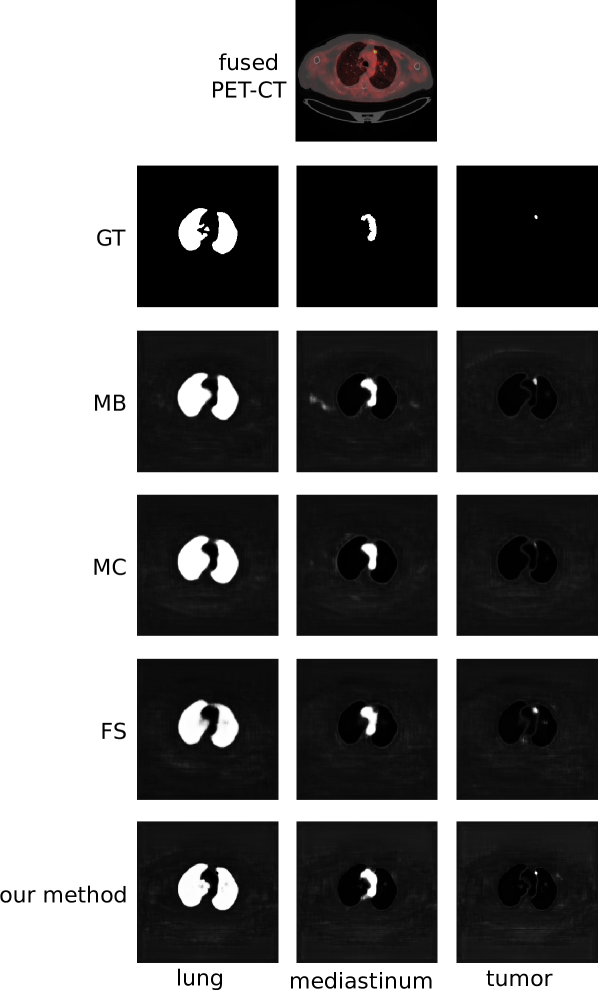

where is the probability that the pixel with observation vector belongs to the region , is the -th element of vector and is the activation corresponding to region . The ‘other’ class (and hence the summation for regions in the denominator of Equation 5) is necessary to formulate the final output of our co-learning CNN as a set of probability maps. The ‘other’ class probability map ensures the sum of probabilities for each pixel has a total of 1 by capturing the probability that a pixel does not belong to any of the ROIs. The use of an additional class to compute the probability of non-ROI regions is a standard formulation that has been used in prior CNN research [73]. Fig. 4 is an example of the probability maps generated for the classes used in our experiments (lung fields, mediastinum, tumors), and the ‘other’ class.

Fig. 5 is a visual comparison of the ROIs detected by our method and by the baselines; a larger version is included as Fig. S3 in the Supplementary Materials. The figure shows that our method consistently detected regions that were a similar size to the ground truth. In contrast, the MC baseline detected fewer pixels (as shown by the tumor region) while the MB and FS baselines detected more pixels than within the region. In particular, the MB CNN gave pixels within the chest wall a high probability of being within the mediastinum.

Our co-learning CNN achieved a higher detection precision, sensitivity, specificity, and accuracy than the MB CNN for fusion across all foreground ROIs individually and collectively. Our explanation for this outcome is that the design of our CNN explicitly fuses features at multiple scales through the multiple co-learning units, which prevents information loss that can occur from the standard pooling (downsampling) operations used for feature map dimensionality reduction in CNNs. In contrast, the MB CNN implements a late fusion approach in which modality-specific feature maps are merged just prior to the reconstruction, meaning that useful complementary information could possibly have already been lost. An examination of Fig. 5 shows that the MB CNN tends to have larger predicted regions compared to the GT (e.g. larger tumor area, extra regions in mediastinum), indicating that the lost complementary information makes the MB CNN less precise.

The MC CNN implements an early fusion approach in which no modality-specific feature maps are derived and where the first convolutional layer combines both modalities to derive fused feature maps. However, as indicated by the metrics in Table II and the images in Fig. 5 this tends to prioritize information from some modalities at the expense of information from the other modality. The clearest example is in the less precise detection of the tumor region, which is barely noticeable in Fig. 5; only the part of the tumor with peak SUV (highest radiotracer uptake) is detected and the less subtle tumor regions are missed altogether.

The FS baseline is another variant of early fusion; the PET and CT modalities are pre-fused via pixel intermixing and the intermixed image is used as the input. It shares a similar weakness to the MC CNN in that the pre-fusion acts to prioritize information from one modality at the expense of the others, resulting in good precision for the lungs (79.11% in Table II) but much lower precision for non-lung ROIs. Examination of Fig. 5 shows that the tumor and mediastinum regions detected by the FS CNN are larger than the GT, indicating that there are a greater number of false positives. Fig. 8 shows that our co-learning CNN produces more consistent ROI detections than the FS baseline, which is sensitive to the selection of the uniform fusion ratio parameter. This suggests that the spatially varying fusion derived within our co-learning CNN may be more robust than a pre-determined fusion parameter setting.